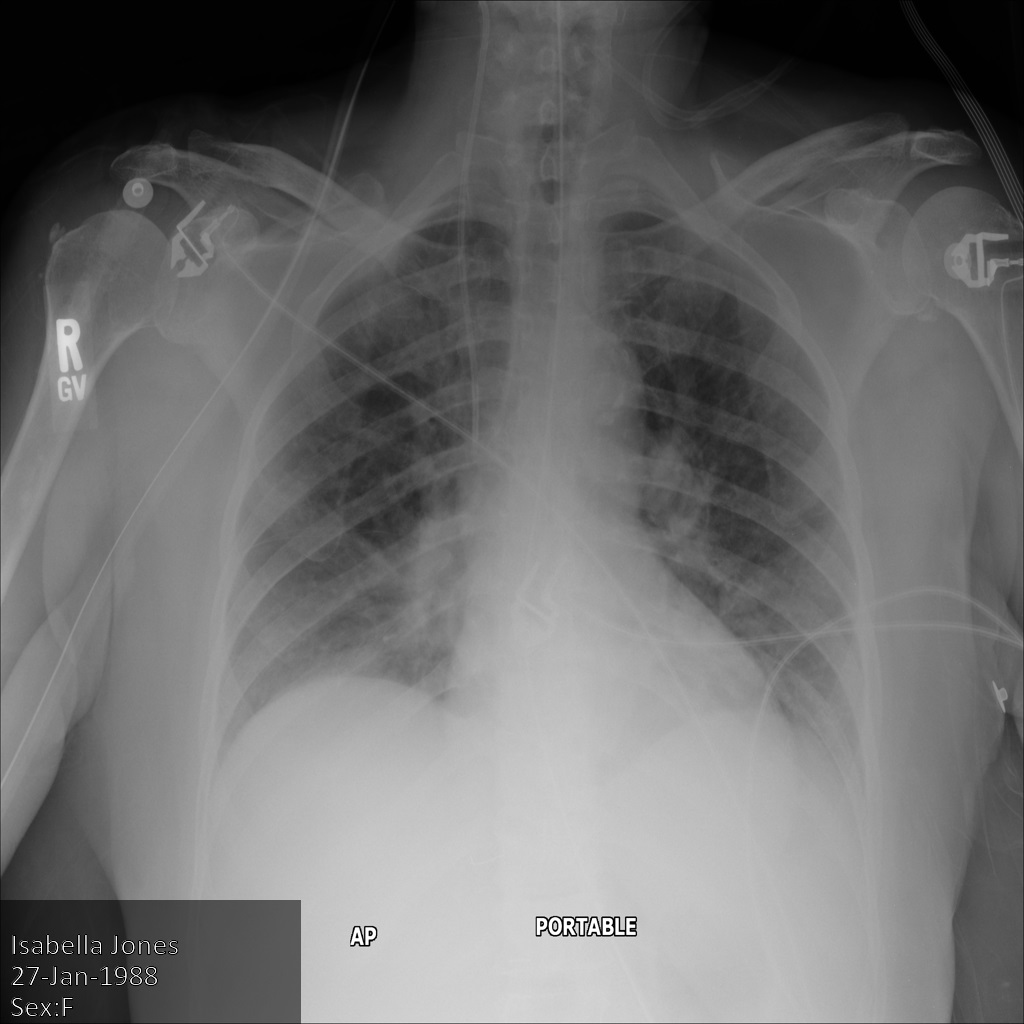

L'immagine seguente mostra una radiografia non oscurata di un paziente:

Dopo aver inviato l'immagine all'API Cloud Healthcare utilizzando

l'opzione REDACT_SENSITIVE_TEXT, l'immagine

viene visualizzata nel seguente modo:

Puoi notare che si è verificato quanto segue:

- Il

PERSON_NAMEin basso a sinistra dell'immagine è stato oscurato - Il

DATEin basso a sinistra dell'immagine è stato oscurato

Il sesso del paziente non è stato oscurato perché non è considerato testo sensibile secondo i tipi di informazioni DICOM predefiniti.